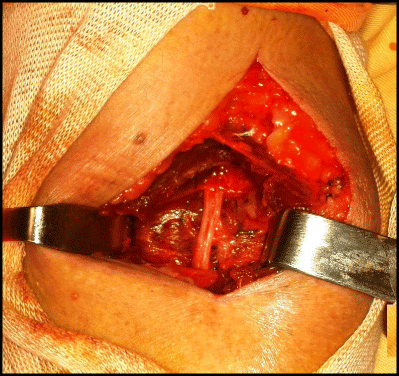

Liberation of the PIN

After excision of the mass, the superficial radial nerve and the PIN were preserved